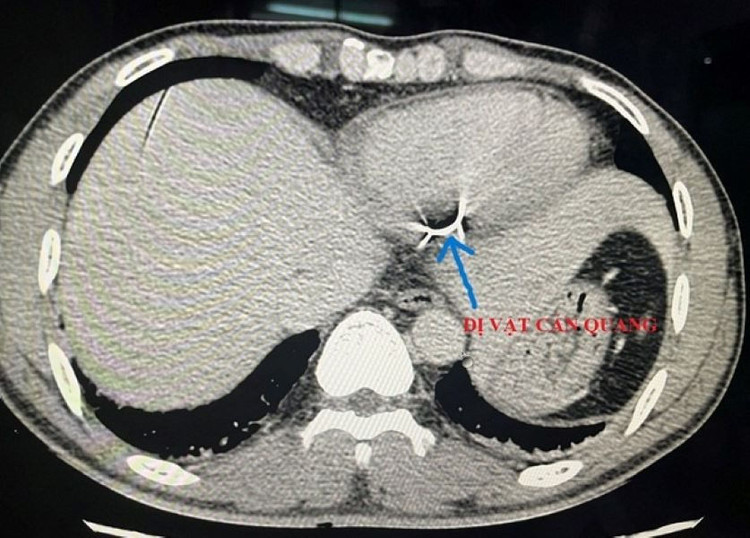

Kết quả cận lâm sàng ghi nhận 1 dị vật dài 4x0.4 cm nằm dọc thành sau thất trái và có thông vào buồng tim. Bệnh nhân được chỉ định phẫu thuật cấp cứu.